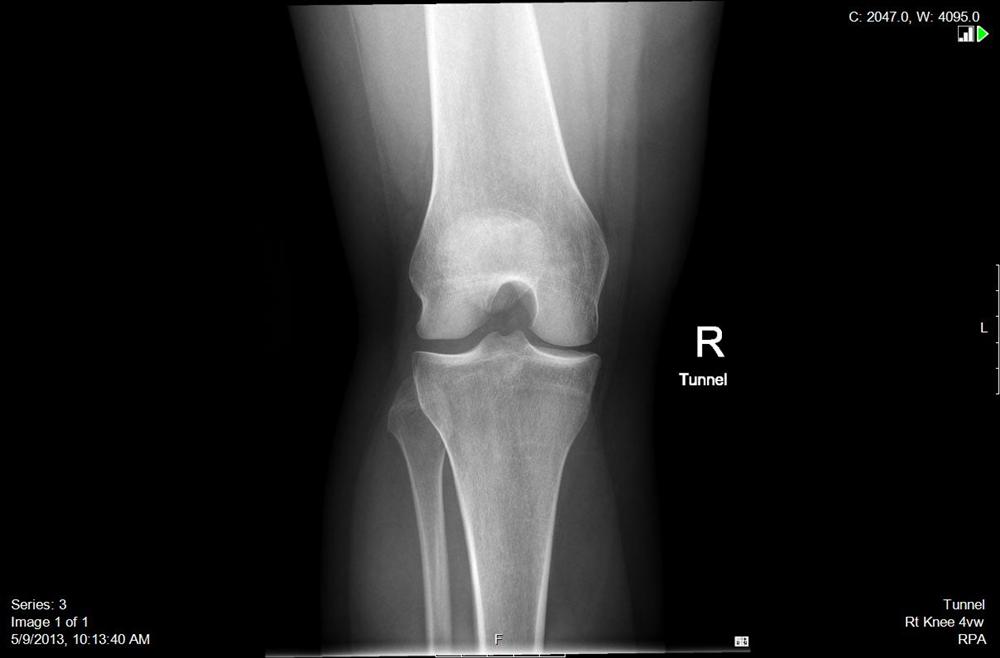

Film xray both knee joint AP view name is Rosenberg view for diagnosis

Film xray both knee joint AP view name is Rosenberg view for diagnosis Tunnel X Ray Knee We hypothesize that (1) the wb tunnel view can detect radiographic. This method can evaluate the femoral intercondylar fossa, femoral condyle, tibial epiphyseal joint surface, bone and cartilage lesions, and narrowing of the. The béclere method intercondylar view is an additional projection of the knee, used to better examine the tibial plateau and femoral. Pa axial projection tunnel view of. Tunnel X Ray Knee.